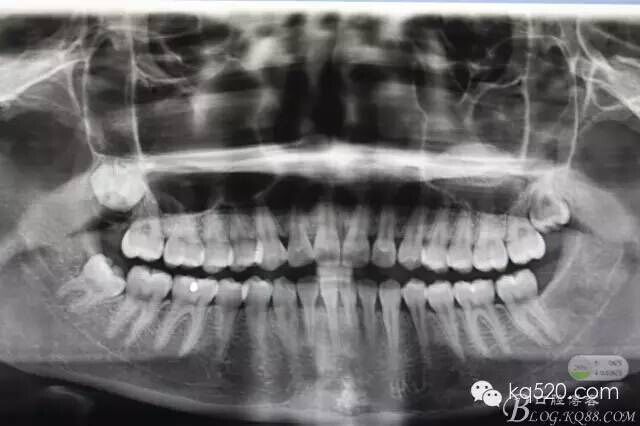

圖1.術(shù)前的x光影像檢查,48近中輕度傾斜。